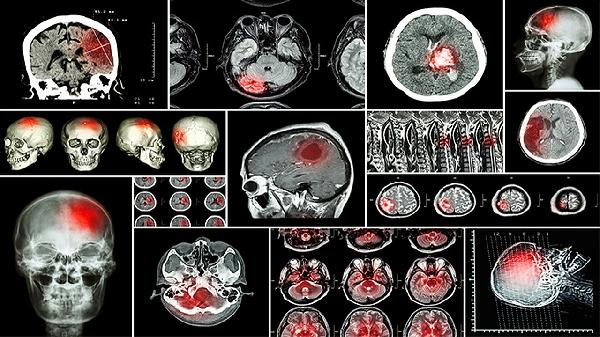

6.密切监测病情变化。定期进行脑脊液检查、头颅影像学检查,评估治疗效果。观察患儿意识状态、生命体征、喂养情况等,及时调整治疗方案。